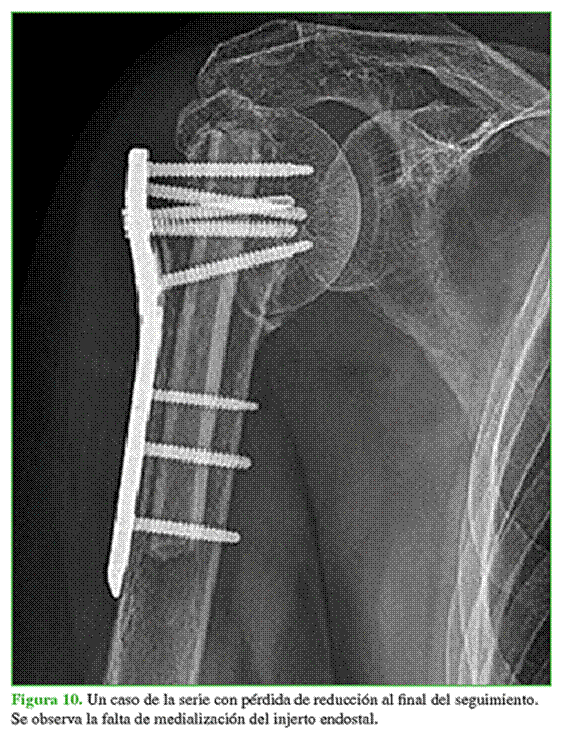

Se obtuvo la reducción anatómica en 10 pacientes, con dos casos de reducción en varo con corrección insuficiente de la bisagra medial por un error en la técnica quirúrgica. El 83% de los pacientes evolucionó sin pérdida de reducción de acuerdo con los cambios tanto en la ACH como en el ACD. El cambio promedio de la ACH entre las radiografías al final del seguimiento y las del posoperatorio inmediato fue de 2,3 mm (rango 0,4-7,24). La diferencia promedio del ACD entre ambos controles fue de 4,92° (rango 1-17°). Dos pacientes presentaron una reducción inadecuada, la cual sufrió además un cambio de ACH >3 mm (3,4 mm y 7,2 mm). En uno de estos casos, se asoció también un cambio del ACD >5° (17°) (Figura 10). Ambos pacientes tenían una reducción inicial en varo, con valores de GCHP de 6,15 mm y 6 mm. La fractura había consolidado al final del seguimiento, en todos los pacientes. No se observaron complicaciones clínicas y ninguno requirió una segunda cirugía.

En la evaluación radiográfica, dos pacientes presentaron una pérdida de ACH de 7,2 mm y 3,4 mm, uno de ellos también con colapso en varo. Ambos pacientes eran mujeres, de 68 y 71 años, con valores de GCHP por encima de 6 (6 y 6,15, respectivamente). La pérdida de reducción se debió a una reducción fallida, en fracturas inestables. Atribuimos estos resultados a un error de la técnica quirúrgica. A pesar de estas fallas radiográficas, los resultados clínicos y funcionales fueron aceptables en ambos pacientes, con valores de elevación anterior de 135° y 110°, rotación externa de 45° y 25°, y un puntaje de Constant-Murley de 76.